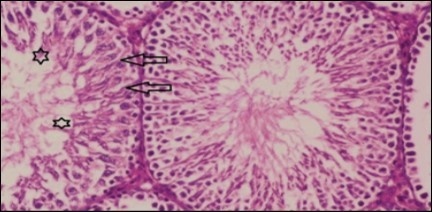

Testis Histopathological Observations

Histological examination of control rats' testis showed normal histological structure of the seminiferous tubules with an increase in the spermatogonia and other spermatocytes compared with the diabetic rats which showed an obvious decrease in the count of germinal cells generally and sloughing of germ cell in the lumen of seminiferous tubules in addition to absence of the mature sperms (Figure 3 and Figure 4). Rats tested of Fenugreek group and those treated with Glimepiride (Figure 5 and Figure 6) presented an increase in the number of spermatogenic cells and mature sperms with few focal necrotic cells. Whereas the combination therapy group showed normal histological structure of the seminiferous tubules with normal spermatogonia, presence of ledying cells and more mature of sperms (Figure 7). STZ reduced testosterone production, suggesting a decrease in the function of both Leydig (testosterone producing cell) and Sertoli (spermatogenesis) cells, which might be caused by a reduction in insulin secretion. These changes are probably due to increased Reactive Oxygen Species (ROS) production by accelerated Advanced Glycation End Products (AGE) formation 31 hexosamine and Protein Kinase C pathway. The administration of Fenugreek seeds to diabetic rats significantly decrease of sperm shape abnormality and improve the sperm count 32. Glimepiride reduced sperm abnormality and increased testis weights and sperm count by its antioxidant action 30. The potential protective efficacy of Fenugreek seed extract when added to Glimepiride was observed on reproductive systems.

Figure 6.Photomicrogragh of testis section of treated rat showing increased number of spermatogenic cells from spermatogonia till spermatozoa (star). Few liquid infiltration in wide interstitial tissue (H&E) (40X).

Figure 7.Photomicrogragh of testis section of treated rat with combination of Fenugreek and Glimepiride showing nearly normal appearance of seminiferous tubules with organized spermatogenesis end with large number of spermatozoa (star). Note, Sertoli cells (arrows). (H&E) (40X).